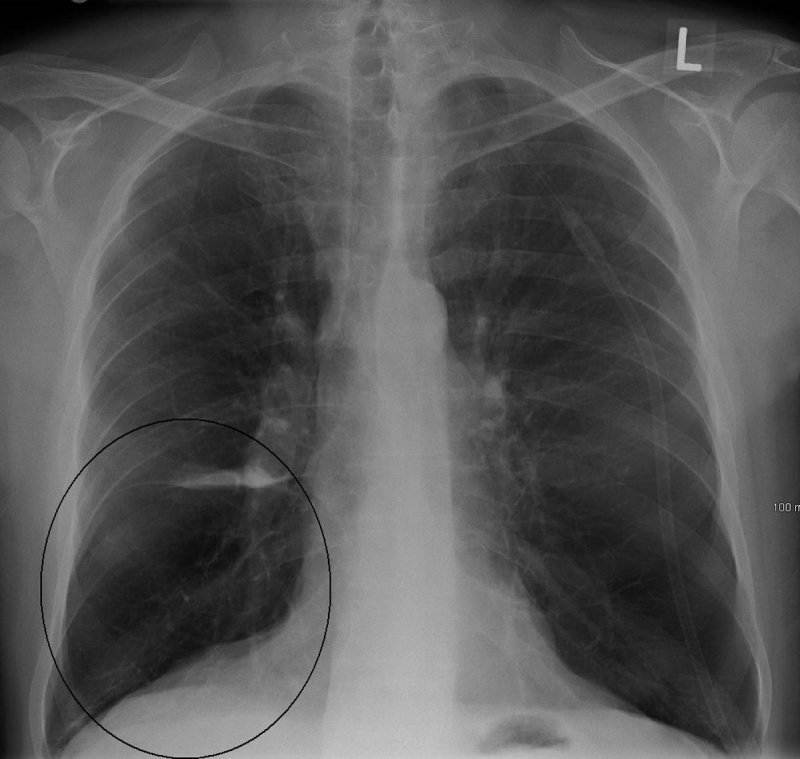

Lung bulla as seen on CXR in a person with severe COPD associated with anti 1 antitrypsin deficiency.

The fine-layer computer tomography of the lungs initiated by Doctor Chris provided the decisive indication: here, he noticed a so-called bullous pulmonary emphysema, i.e. there are smallest, thin-walled and very vulnerable bubbles (air sacs or alveoli) in the lungs tissue. These bubbles are airfilled and may also easily rupture without significant changes in ambient (atmospheric) pressure.

Bullae may develop in case of a chronic obstructive pulmonary disease (COPD). Tobacco consumption over many years is one of the principal reasons for a COPD. It is true that Matthias had already given up smoking three years ago. However, he had smoked for over 20 years. During this time a bullous pulmonary emphysema (consisting of lots of small Bullae) has developed.

Emphysema cavities mostly develop in the upper part of the lungs. Clinically speaking, a bullous lung emphysema is inapparent. Some people notice exertional dyspnea as the first symptom (they do not get enough air when they exercise or climb the stairs), a spontaneous pneumothorax (ruptured lung) can also result from this disease.